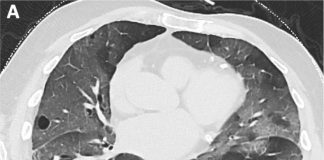

57-year-old male patient with fever, cough. No previous medical history. Potential exposure to Covid-19 patients.

Respiratory

failure (hypoxemia and hypocapnia). Leukocitosi. Nasal swab positive for

SARS-CoV-2.

HRCT